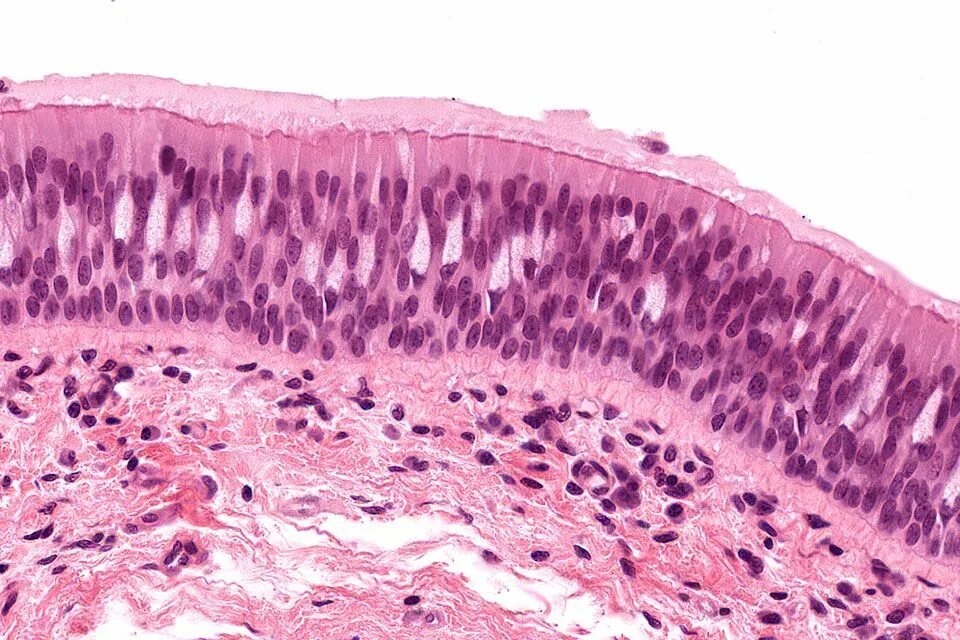

Нексус это гистология